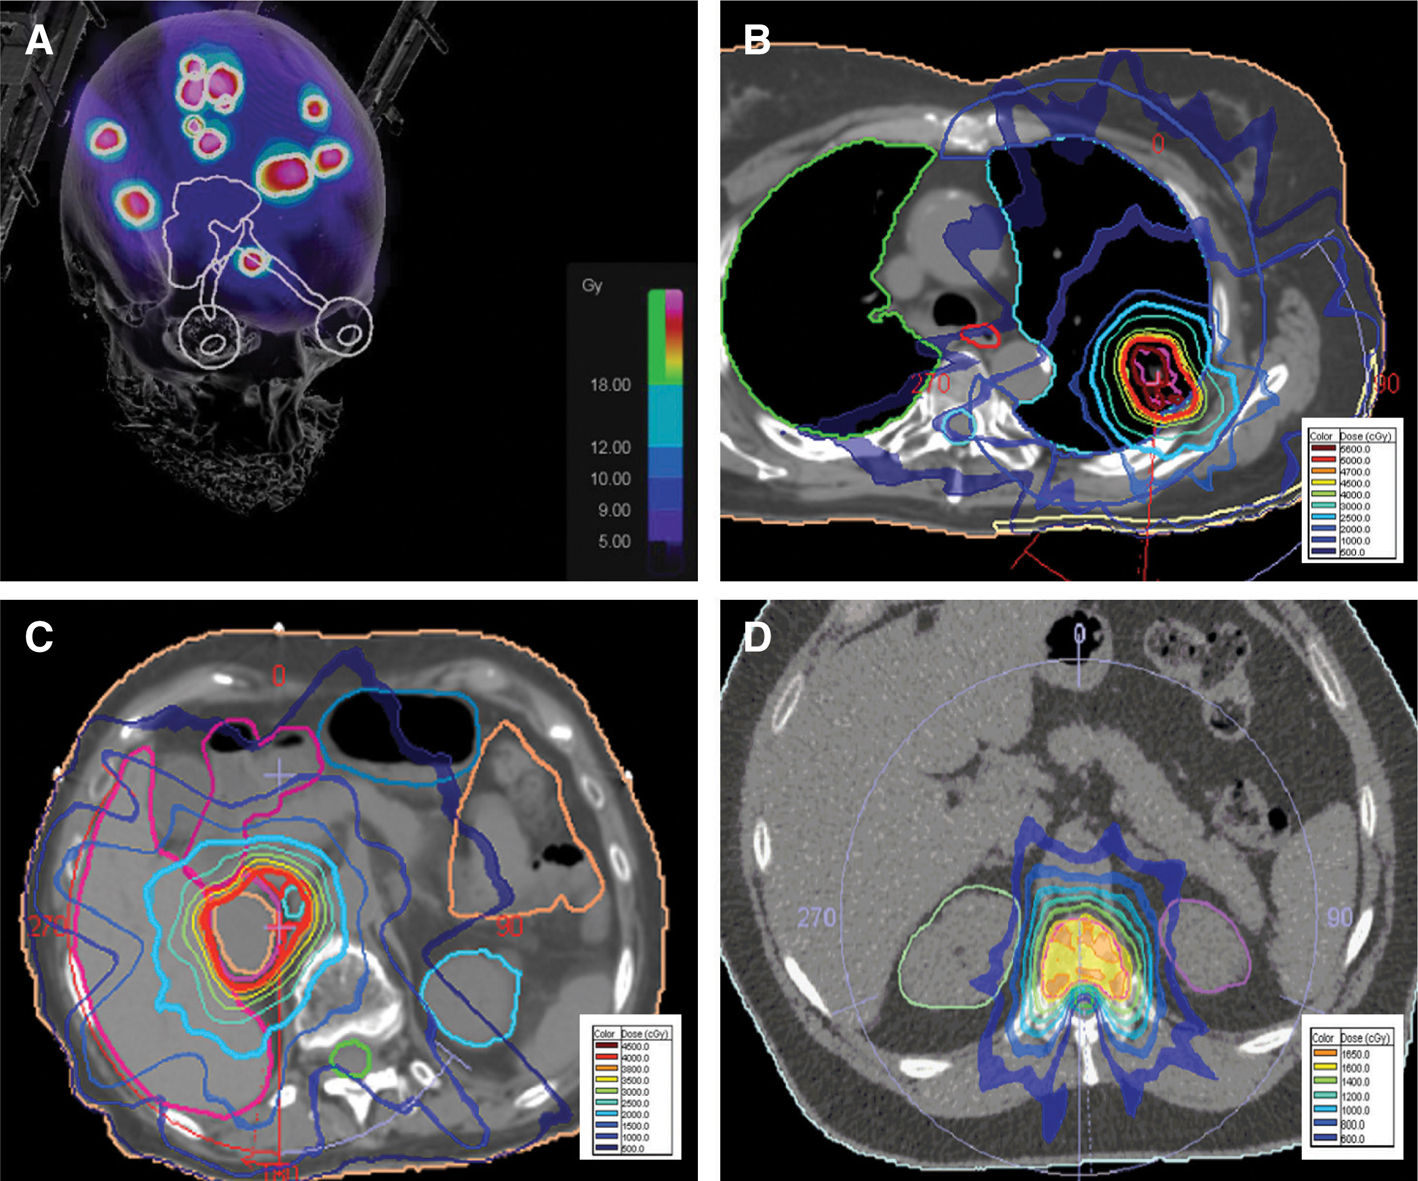

On the other hand, there have been significant advancements in RT with evolution of imaging techniques, such as high-resolution computed tomography (CT), magnetic resonance imaging (MRI), positron emission tomography (PET), as well as advances in radiation delivery techniques. Two-dimensional techniques evolved to three-dimensional techniques with implementation of CT planning scans. The development of inverse planning such as intensity-modulated radiotherapy (IMRT) and volumetric-modulated arc therapy (VMAT) have allowed for even more precise RT delivery while sparing normal tissues and decreasing associated toxicity (13). High precision with patient immobilization, imaging guidance, and steep dose gradient allows for high-dose treatment delivery, which is most suitable for melanoma. Stereotactic radiosurgery (SRS) and stereotactic body radiation therapy (SBRT) are two examples of high-dose radiation therapy with high precision delivery (Figure 1). SRS refers to a precisely delivered single large dose of radiation achieved by multiple noncoplanar beams converging on a radiographically defined target (14). For this type of RT delivery, there is a steep decline of radiation dose just outside the target volume, thereby limiting the dose to normal critical structures. It is commonly used for treating melanoma brain metastasis. SBRT refers to high dose per fraction precise RT over approximately 2–5 treatment sessions. This dose fractionation scheme is particularly useful for patients with oligometastatic disease, such as lung, bone, liver, or adrenal metastasis.

Figure 1 Examples of SRS and SBRT treatment plans for melanoma metastasis: A) stereotactic radiosurgery (SRS) for multiple brain metastases; B) stereotactic body radiotherapy (SBRT) for lung metastasis; C) SBRT for adenral metastasis; and D) SBRT for spine metastasis.